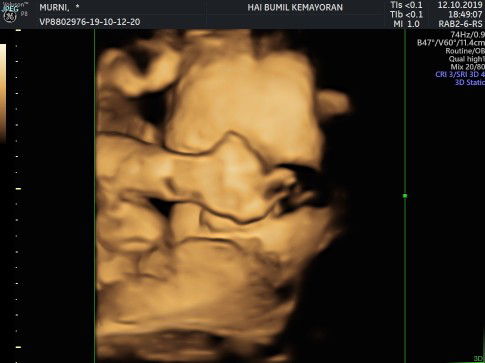

Hallo bunda, salam kenal yaaa ? sekarang usia kandunganku sudah 7bulan 28week ?? ini hasil si dd gemas yg lg di usg malu2 kucing bun ? gak mau dliatin mukanya ?